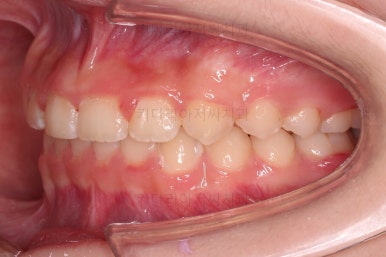

마무리를 해줍니다.

앞니 각도가 매우 좋아졌고요.(옥니 개선) 위아래 앞니가 덮는 정도도 개선이 되었어요.(과개교합, 딥바이트)

엉성했던 어금니 맞물림도 매우 좋아졌어요.(앵글씨 2급 부정교합 개선)

전후사진을 비교해 볼게요.